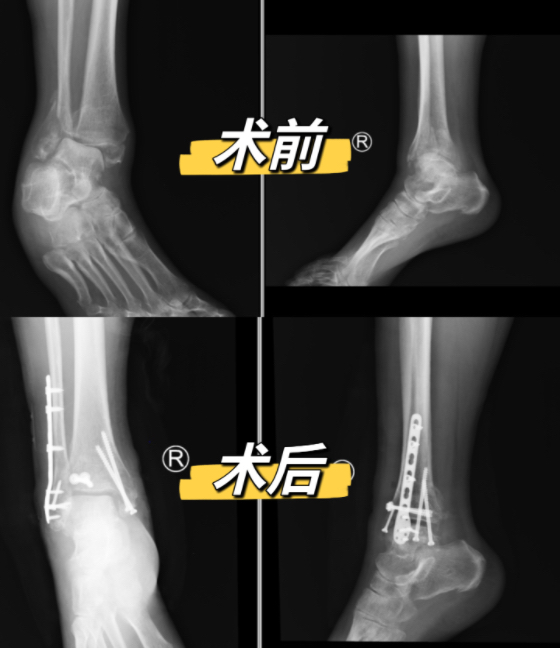

患者术前、术后对比图

陈旧性三踝骨折治疗的另一个难点在于恢复踝关节正常骨性结构,因病程较长,患者折断的骨折块已在错误的位置愈合,术中需截骨后再行复位,由于骨折端失去恢复正常骨结构的标志物,如没有丰富的治疗经验和充分的术前准备,很可能复位后依然存在畸形复位,影响手术效果。为确保手术效果,完善患者右踝CT后在计算机上进行三维重建并截骨模拟,充分了解患者病变情况,争取做到手术万无一失。经过周密的准备,医师团队经过两个小时的时间顺利完成了手术,术后第一天患者便可自主活动右踝关节,他表示:“我的腿直了,动起来也不痛啦!”